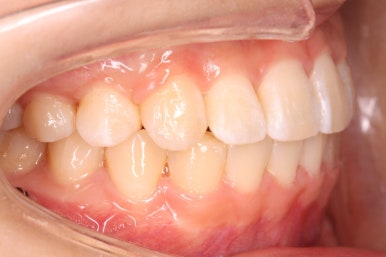

치아는 매우 가지런해졌고, 과개교합도 개선이 되었으며 뻐드러진 앞니 각도도 정상적으로 회복이 되었습니다.

치아가 가지런해졌습니다.

뻐드러진 앞니가 정상적인 각도로 회복되었습니다.

전반적인 치아들의 위치가 뒤로 이동하였습니다.

뻐드러진 치아가 뒤로 들어가면서 돌출감이 개선되었습니다. 옆모습에서 인중 라인의 형태 및 아랫입술 ~ 턱끝까지 이어지는 S라인의 느낌이 좋아졌습니다.

삐뚤어진 양도 꽤 되고, 과개교합, 치아 뻐드러짐도 있었는데 비발치 교정으로 충분히 원하는 목표를 당성했다고 생각합니다.